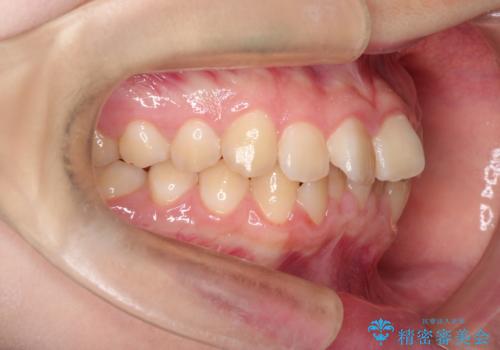

上下の前歯のガタガタを目立たず治したい インビザラインによる見えない矯正

- 上下の前歯のガタガタを治したいとのことで来院されました。

上下の歯と歯の間をわずかに削り、並べる計画としました。

上下の正中が一致していませんが、受験を控えているためご本人の希望もあり、いったん終了とさせていただきました。